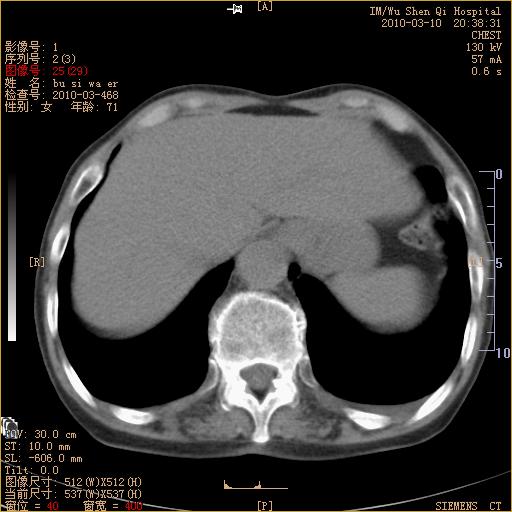

以下是引用随光逐影在2010-3-11 0:41:00的发言:[br]1)考虑左肺及右肺上叶继发性肺结核并左肺炎症感染。2)左侧支气管内膜结核可能;建议必要时行纤支镜检查。3)肺气肿。4)心包膜增厚(或少量心包积液)。5)左侧胸腔积液。